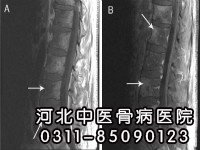

怎样治疗脊椎骨骨髓炎?治疗脊椎骨骨髓炎是一个综合系统的治疗过程,需要根据患者病情的实际情况而制定治疗方案。

怎么彻底治疗脊椎骨骨髓炎?用什么方法才能见效快?所谓彻底治疗,也就是我们常说的临床治疗,让患者摆脱不适症状的困扰,最大程度恢复健康,并控制愈后各种并发症的发生机率。